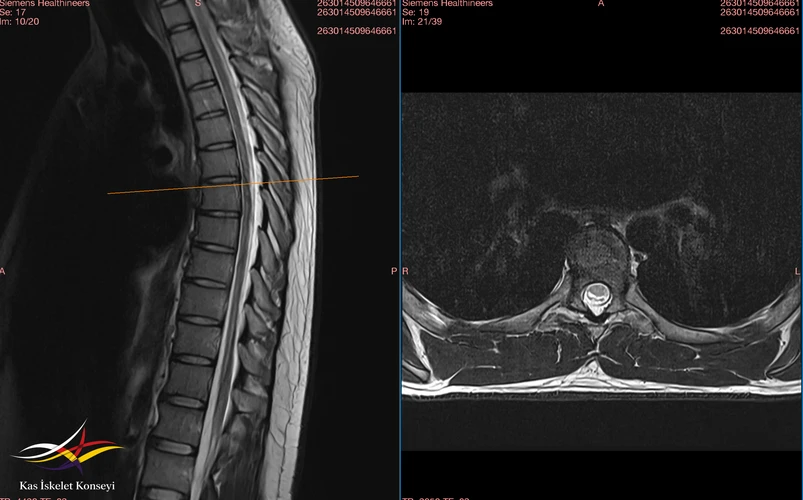

Torakal MR : ½ alt yarımda spinal kord santralinde sadece sagittal T2 serilerde vizualize edilen şüpheli sinyal artışı izlenmiştir. Myelopati ? T9-10 sağ nöral foramen 5 mm perinöral kist. Faset eklem dejenerasyonu.

Resim 1. Torasik MRG.